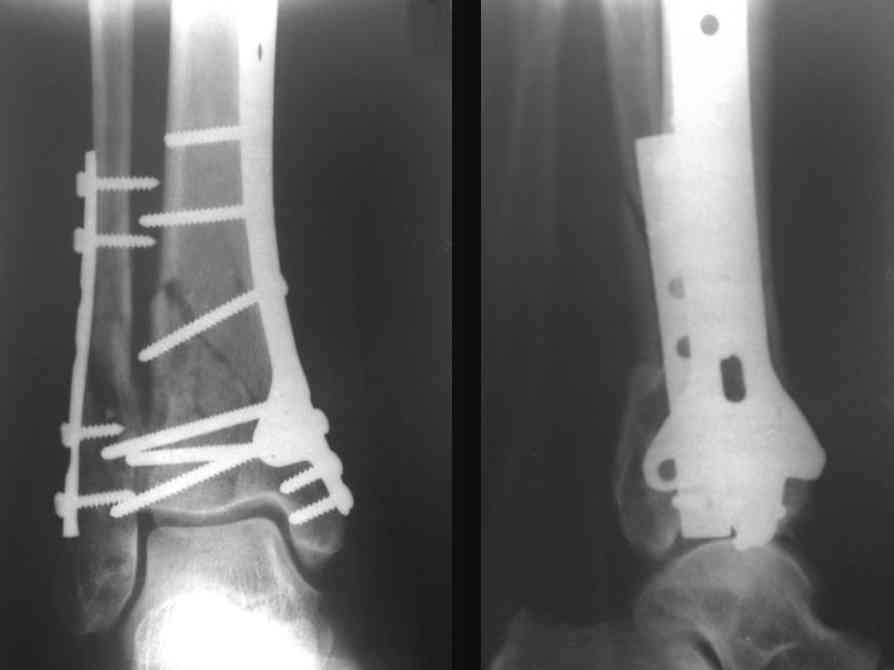

На рентгенограммах типичный перелом пилона по типу С-3. есть опыт до 100 открытых опреаций у нас в клинике. 20 примерно в год. Принцип один -все внутрисуставные переломы нуждаются в открытой репозиции и внутренней стабильной фиксации. При поступлении КТ не надо, так как получается только нагромождение костей. Истинной картины нет. Главное восстановить длину малоберцовой кости - это ключ к успеху. При поступлении меньше всего надо думать о сосудистых расстройствах, т.к. сама операция и репозиция даже сначала частичная даёт улучшение сосудитых нарушений. Причём очень быстро. Операция в 2этапа. При поступлении доступ позади наружной лодыжки, причём обязательно. После этого репозиция малоберцовой кости и фиксация пластиной 1/3 трубки под винт 3,5. Дренаж и любой аппарат наружной фиксации. Затем после спадения отёка на 5-7-10 день аппрат снимается и дугообразный разрез спереди от медиальной лодыжки 10-12 см. Главной чтобы расстояние между 1 и вторым разрезом было не меньше 7-8 см. Тогда не будет некрозов лоскутов. Таранная кость используется как матрица на неё укладываются отломки и фиксируются пицами. Ренг-контроль. Отломки лежат все отдельно, но ничего не высыпется. При переломах С-3 всегда нужна костная пластика (из крыла). Фиксация пластиной лист клевера простой или LCP. Гипс не нужен. Дренаж до 48 часов. Операция длится 3-4 часа обязательно без жгута. Посылаю примерно такой же случай.

Отправитель: Дрягин В. 04 Январь 2007, 09:01

Послала ещё два снимка, если не пройдут, пошлю ещё. Дрягин. Если есть вопросы, готов ответить.